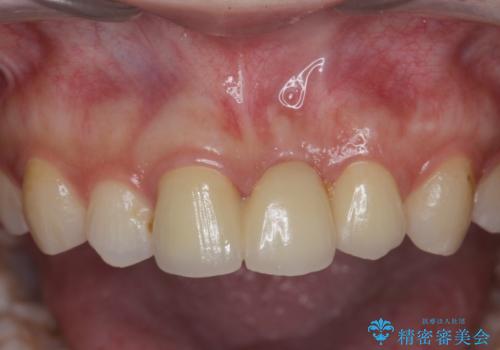

長期的な予後を見通すことが難しかったので、亀裂のある前歯の抜去を行いブリッジで審美性・機能性の回復を行いました。

- 36.3万円(仮歯・ジルコニアクラウン×3)費用は治療当時の料金となります